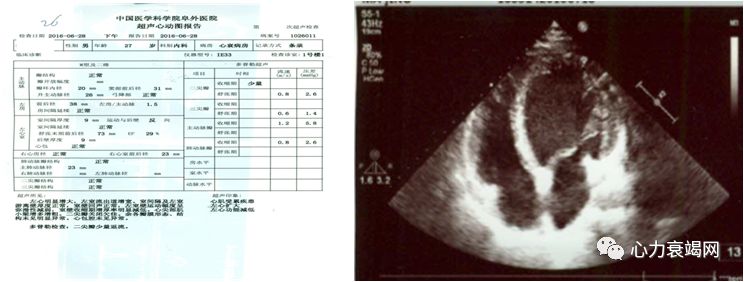

心脏超声(6-28)

LVD73mm LA:38mm

RV23mm LVEF29%

室间隔和左室游离壁厚度正常

室壁运动弥漫减弱

心尖部肌小梁增多增粗

二尖瓣少量反流